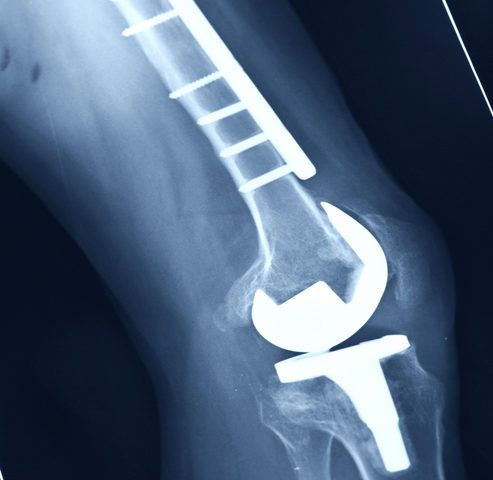

Recovering from A Total Knee Replacement

Have you ever been in so much pain and stiff, that you have trouble with your mobility? Well, that could be due to your joints. Joints can be damaged by arthritis, chronic conditions, or injuries. Arthritis or simply years of use may cause a lot of wear and tear on your joints. Thus causing pain,…

Recovering from Joint Replacement Surgery

Have you experienced pain and stiffness that was so extreme that you had trouble with your mobility? Your joints being injured or not working properly could cause those symptoms, and more. Joints can be damaged by arthritis, degenerative conditions, or injuries. Arthritis or simply years of use may cause a lot of wear and tear…